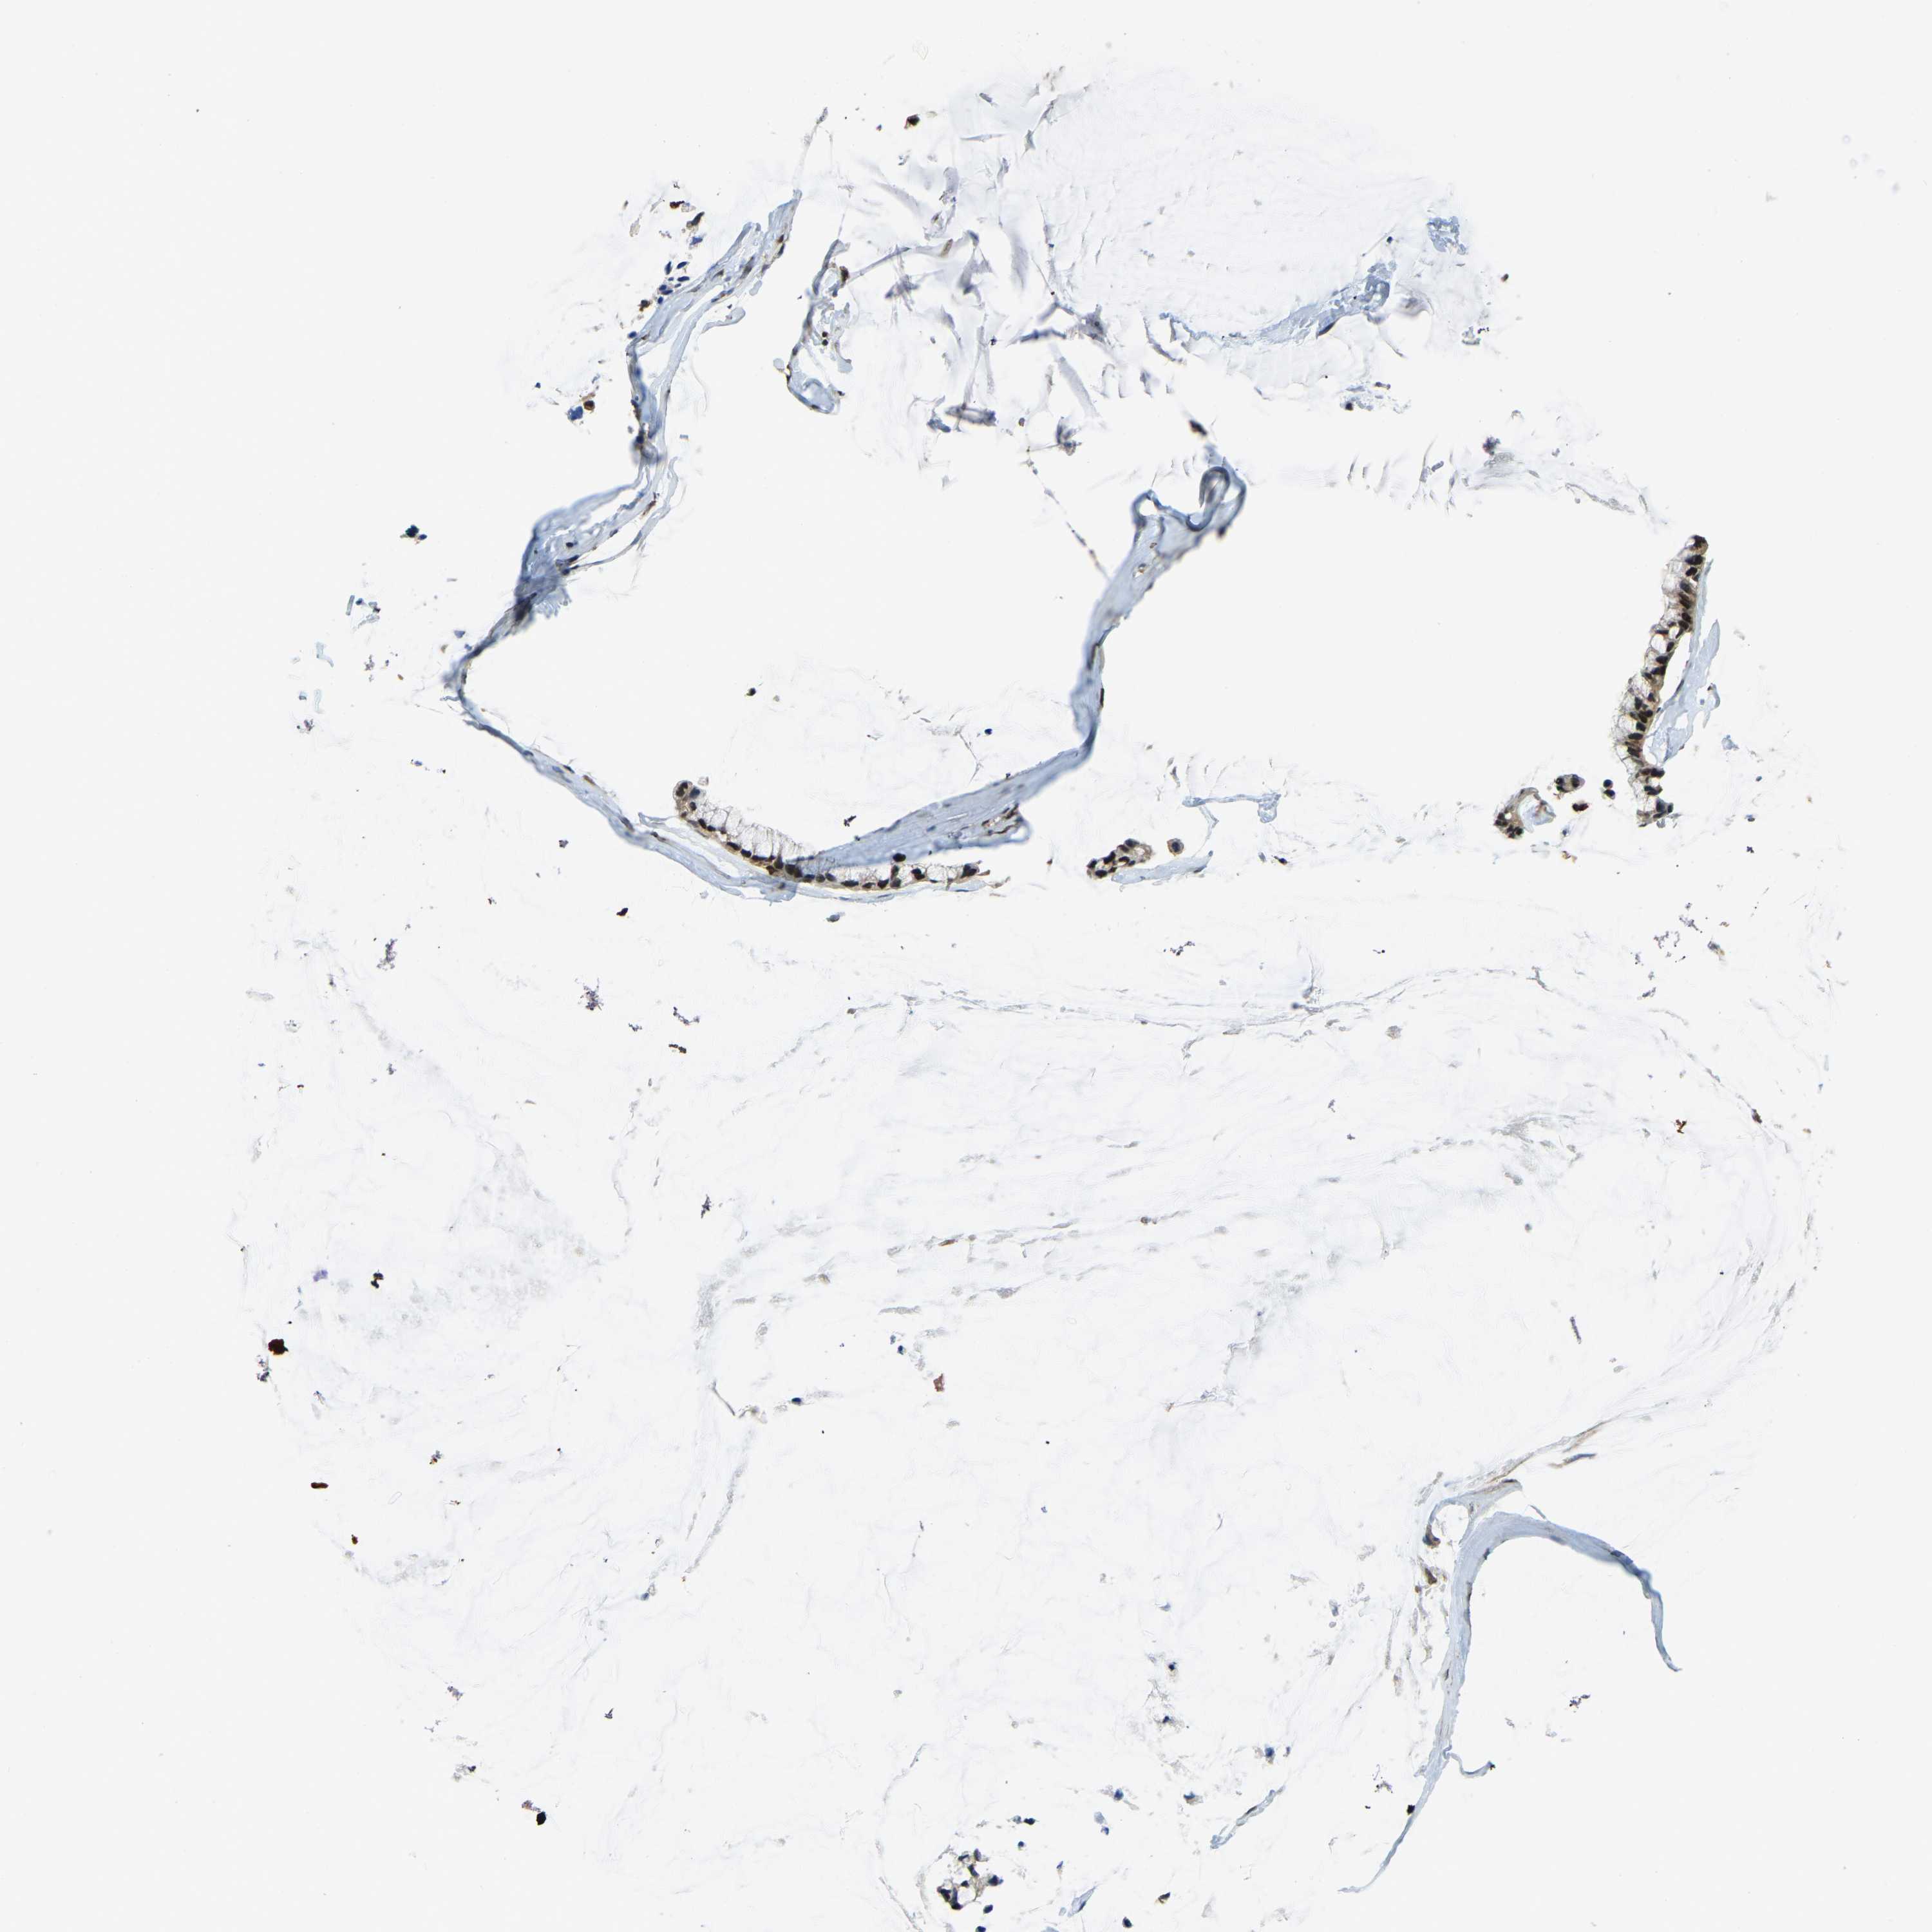

OVARIAN CANCER - Protein expressioni

A mouse-over function shows sample information and annotation data. Click on an image to view it in a full screen mode. Samples can be filtered based on level of antibody staining by selecting one or several of the following categories: high, medium, low and not detected. The assay and annotation is described here.

Note that samples used for immunohistochemistry by the Human Protein Atlas do not correspond to samples in the TCGA dataset.

Antibody stainingi

Antibody staining in the annotated cell types in the current human tissue is reported as not detected, low, medium, or high, based on conventional immunohistochemistry profiling in selected tissues. This score is based on the combination of the staining intensity and fraction of stained cells.

Each image is clickable and will lead to virtual microscopy that enables deeper exploration of all samples and also displays staining intensity scores, fraction scores and subcellular localization as well as patient and tissue information for each sample.

Antibody HPA019223

Staining

High

Medium

Low

Not detected

Intensity

Strong

Moderate

Weak

Negative

Quantity

>75%

75%-25%

<25%

None

Location

Nuclear

Cytoplasmic/membranous

Cytoplasmic/membranous,nuclear

Cystadenocarcinoma, serous, NOS

Carcinoma, endometroid

Cystadenocarcinoma, mucinous, NOS

Carcinoma, NOS